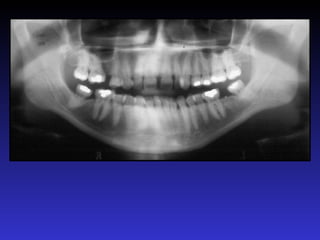

2. Các mốc giải phẫu trên phim toàn cảnh

1. Xoang hàm

2. Hố chân bướm hàm

3. Xương chân bướm

4. Gai bướm

5. Cung xương gò má

6. Lồi khớp xương thái dương

7. Đường khớp gò má thái dương

8. Mỏm gò má

9. Lỗ ống tai ngoài

10. Mỏm chũm

11. Hố sọ giữa

12. Bờ viền ngoài ổ mắt

13. Bờ dưới ổ mắt

14. Lỗ dưới ổ mắt

15. Ống dưới ổ mắt

16. Hốc mũi

17. Vách ngăn mũi

18. Gai mũi trước

19. Xương cuốn dưới

20. Lỗ răng cửa

21. Vòm miệng cứng

22. LồI củ xương hàm trên

23. LồI cầu

24. Mỏm vẹt

25. Khuyết sigma

26. Hố giữa khuyết sigma

27. Mỏm trâm

28. Cột sống cổ

29. Gờ chéo ngoài

30. Ống răng dưới

31. Lỗ ống răng dưới

32. Gai Spix

33. Lỗ cằm

34. Hố tuyến dưới hàm

35. Gờ chéo trong

36. Hố cằm

37. Gờ cằm

38. Gai cằm

39. Xương móng